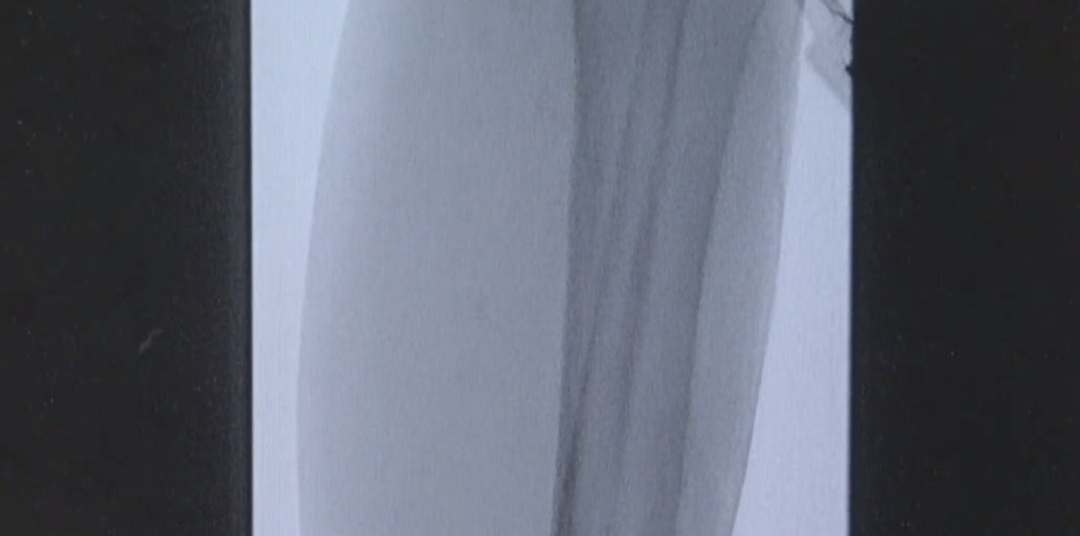

通过血管造影

医疗团队在周阿姨下肢的腘动脉以下

都没有发现血流信号

确认病灶后便马上为她的血管进行“疏通”